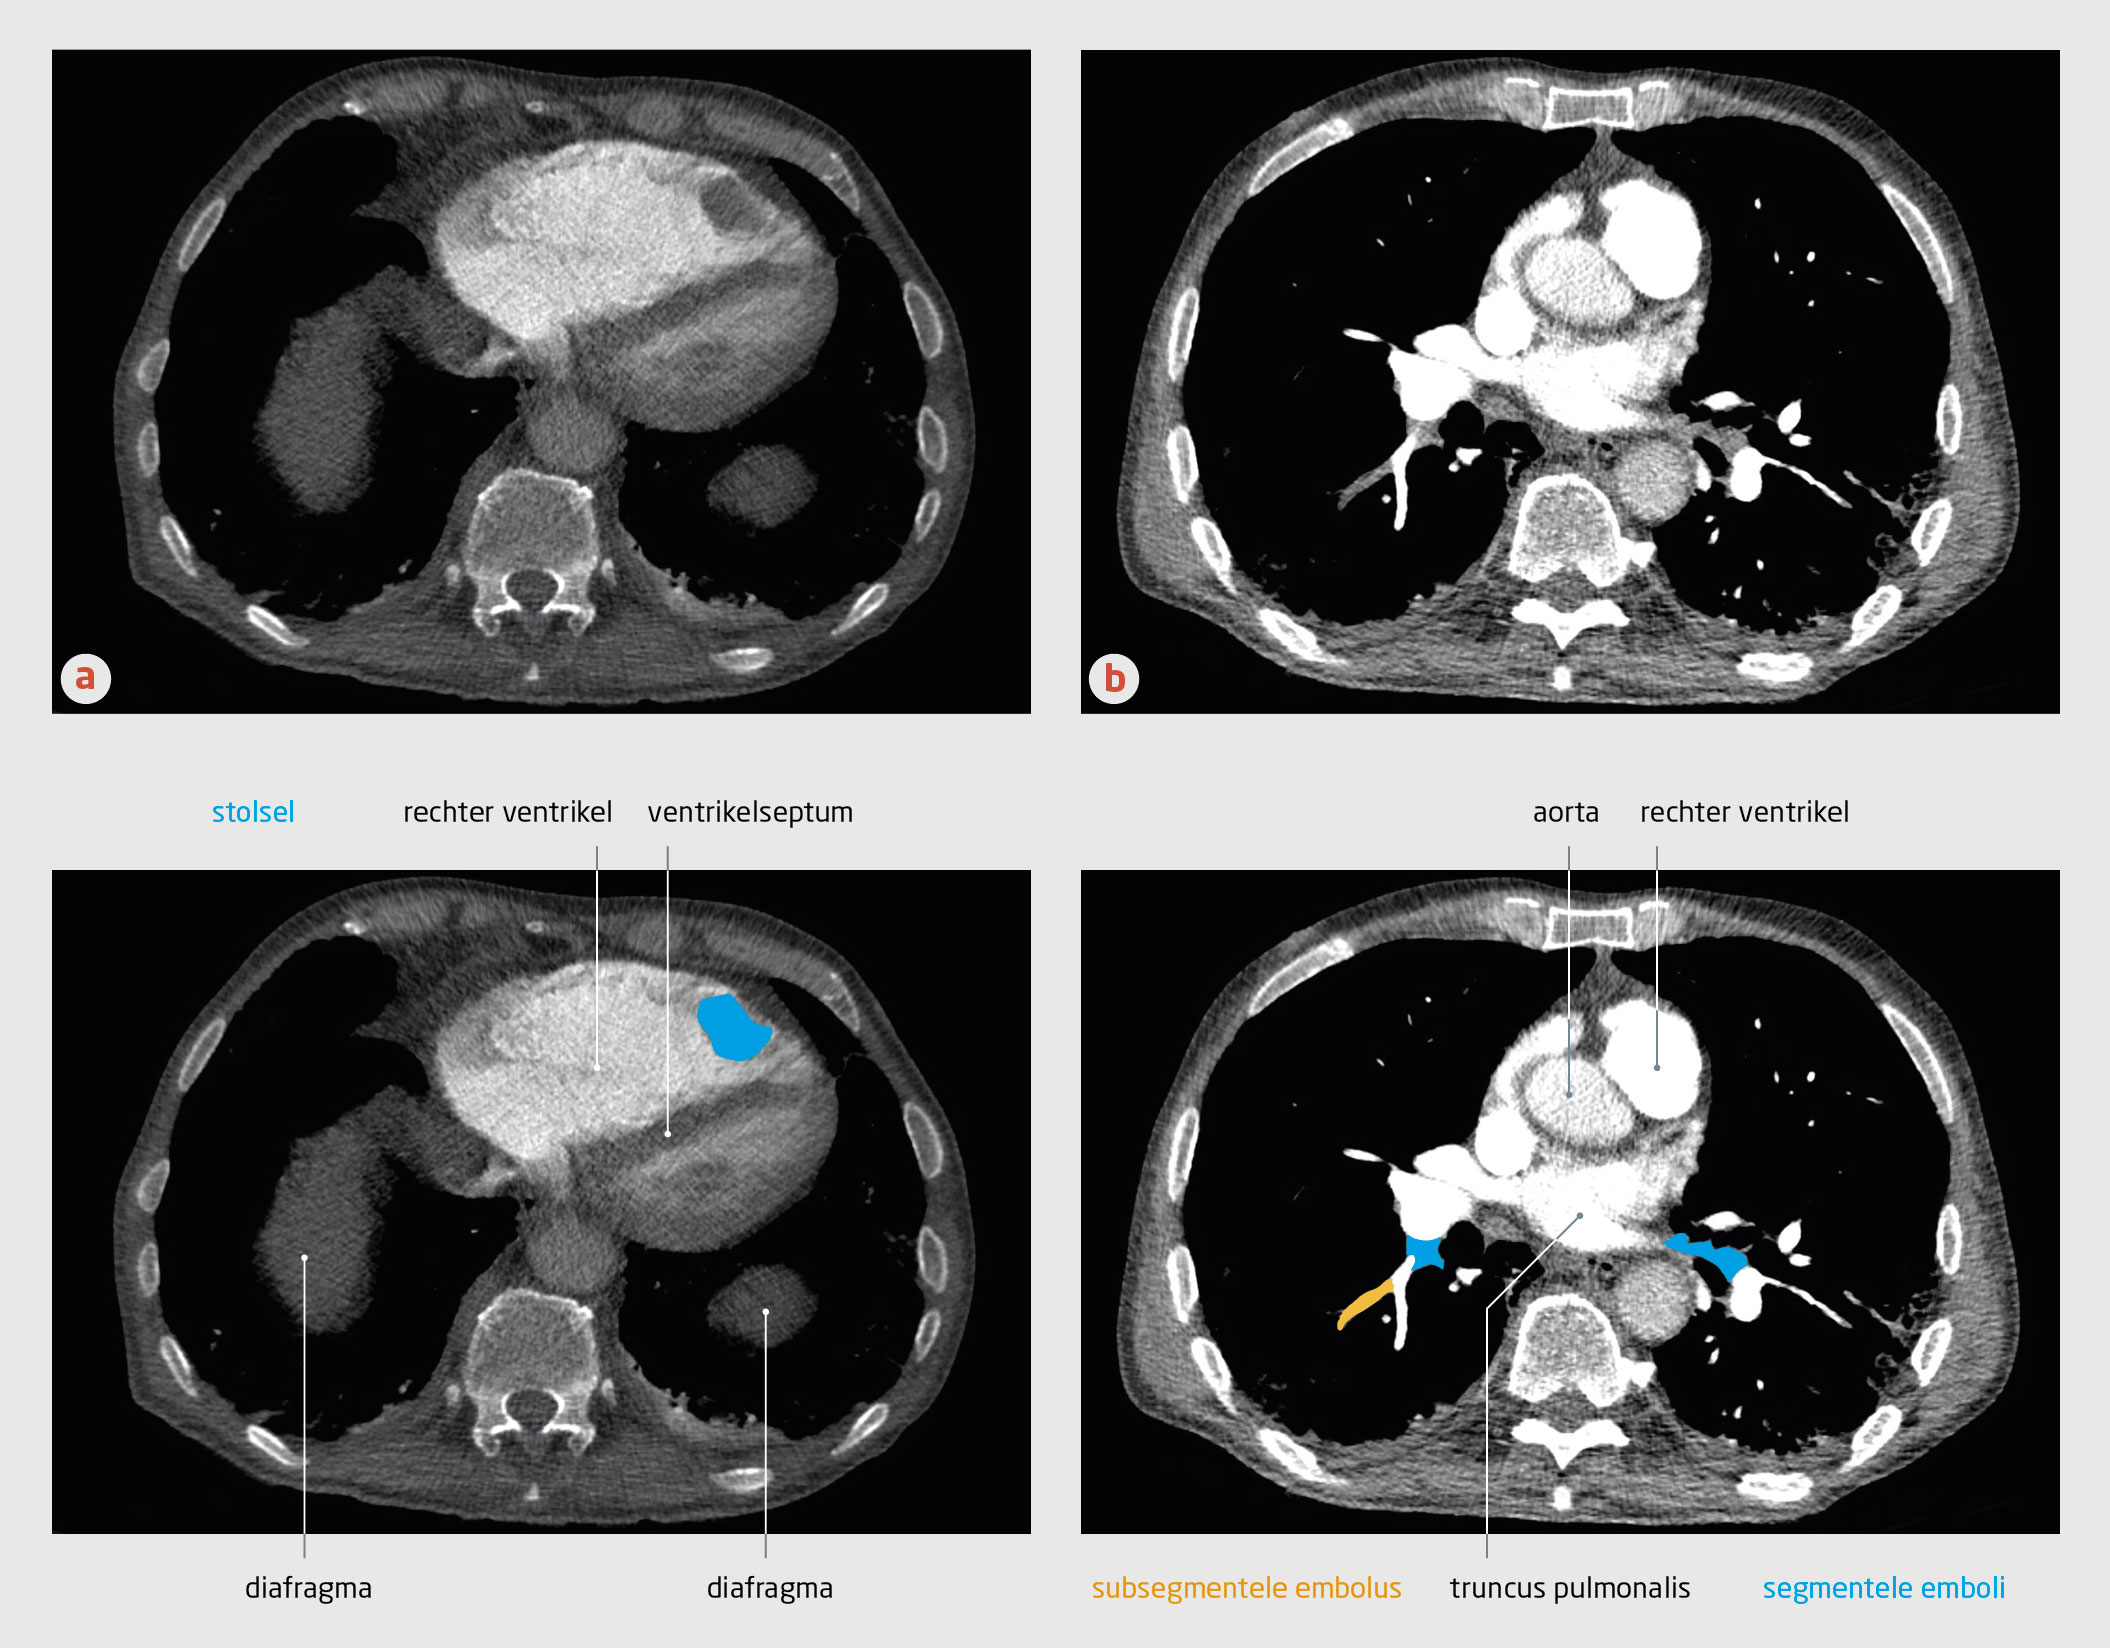

In de verklarende tekening bij figuur 3b van dit artikel zijn enkele structuren onjuist aangegeven. In het onderschrift bij deze figuur staat ten onrechte dat in figuur 3b segmentele embolieën zichtbaar zijn. Hieronder staat de juiste figuur met het correcte onderschrift.

Figuur 3

CT-angiografie van de thorax van patiënt C

CT-angiografie met contrast van patiënt C (transversale coupe). (a) In de rechter ventrikel bevindt zich een stolsel. De rechter ventrikel is vergroot en er is sprake van septumdeviatie, passend bij overbelasting van de rechter ventrikel. (b) Bij deze patiënt was sprake van subsegmentele longembolieën.

Gezien dit klinische beeld, de D-dimeerwaarde van 3,3 mg/l en een sterke verdenking op longembolie werd op grond van het YEARS-algoritme (afkapwaarde voor D-dimeer: 0,5 mg/l) een CT-A verricht. Deze liet multipele segmentele en subsegmentele longembolieën zien, alsmede een stolsel in de apex van de rechterventrikel met een diameter van 3 cm (figuur 3).

CT-angiografie met contrast van patiënt C (transversale coupe). (a) In de rechter ventrikel bevindt zich een stolsel. De rechter ventrikel is vergroot en er is sprake van septumdeviatie, passend bij overbelasting van de rechter ventrikel. (b) Bij deze patiënt was sprake van zowel segmentele als subsegmentele longembolieën.